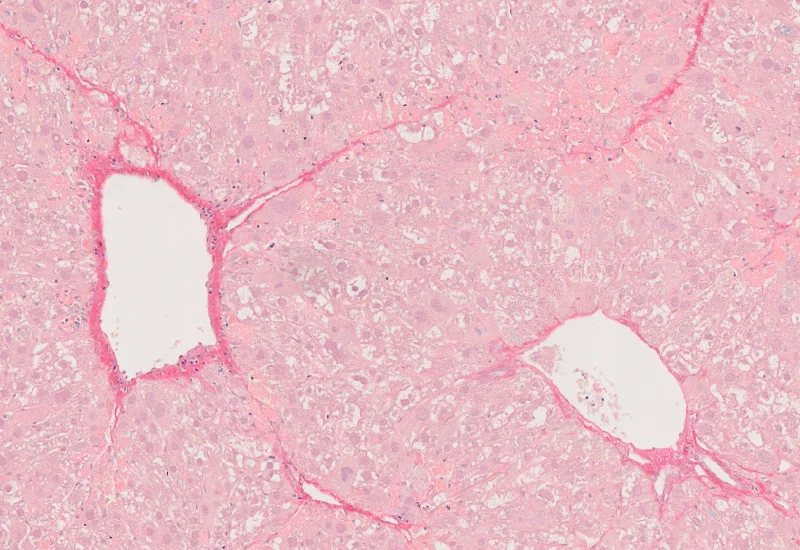

Original Image